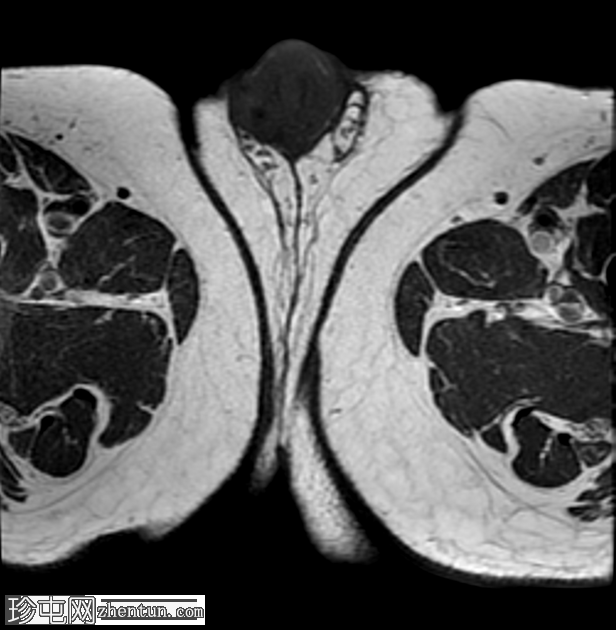

轴位

T1加权像

龟头可见不规则形状的软组织肿块,增强后明显强化,并伴有扩散受限。该肿块侵犯尿道海绵体,导致远端尿道狭窄和上游尿道扩张。

左侧腹股沟可见多个肿大的病理性淋巴结,右侧可见较小的非特异性淋巴结。